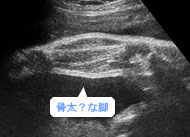

将来はアスリートかな?ふくらはぎの2本の骨もずいぶん太くなりました。(妊娠36週)